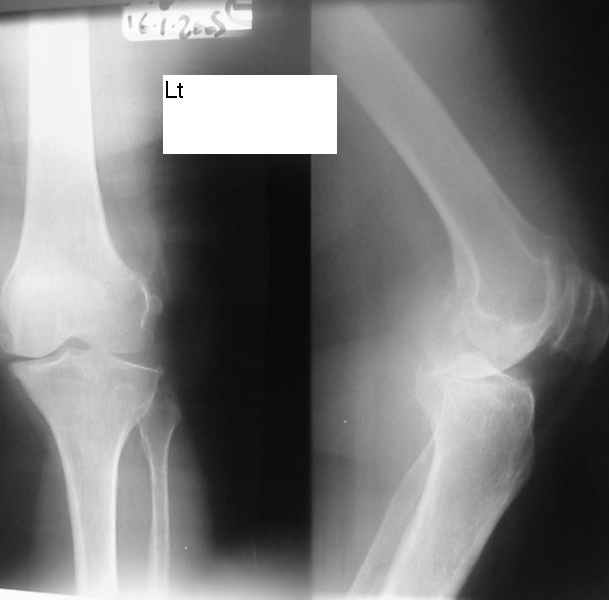

Dorogie Kollegy,Ko mne obratilas' bol'najia, ei 64 goda, ona stradaet ot dvuhstoronnego varusnogo gonoartroza, ei bila vipolnena Visokajia Ostotomjia goleny sprava 01.06.2004, zona osteotomii ne sroslas', plastina bila udalena 12.09.2004 (vidimo iz-za ee nestabilnosti), zona osteotomii tibia bila fixirovana 3-mjia shurupami. Seachas sylno bespokoyat boly v dvuh sustavah, hodit s trudom s pomoshyu Walker, a voobshe ona seachas na invalidnoi kolyaske. Podzkazite, pozhalusta, kak mozno ei pomoch' (snimky prilagayutsa)

U bol'nogo non-union osteotomii tibii. V vozraste 64 let, sdelal bi sleduiezhee:

Work out, proverit', net li infection: ESR, CRP, White cell Scan. Esli infection net togda est' dva varianta:

1. I predpochel bi ego: Total Knee Arthroplasty. Nuzhen budet Revision ( Long stem) tibial Component.

2. Ne sovetuiu delat' geroicheskix postumkov v otnoshenii Non union. Tut est' mnogo problem, ved' esteotomia provedena ne pravili'no s tochki zrenia deformazii. Orientazia ploskosto kollennogo sustava xotia ne ploxa v sagital'noii ploskosti, no vo frontl'noi idet sil;noie otklonenie narozhu i vniz. A nam tida ne nado.